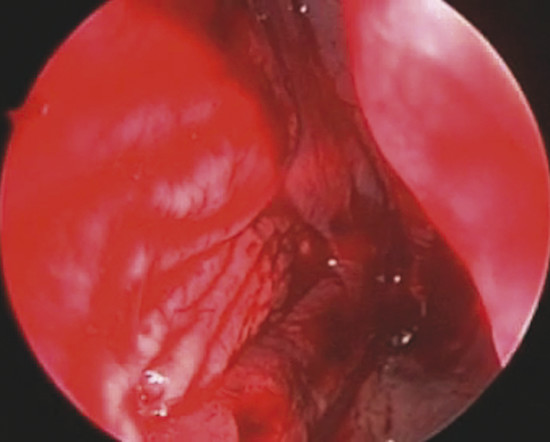

Through a hemitransfixion incision, mucoperichondrial and mucoperiosteal layers are extensively elevated on one side of the nasal septum, from the inferior edge of quadrilateral cartilage up to the choana, nasal floor, and 1 cm from the nasal roof (Fig. 19‑2).